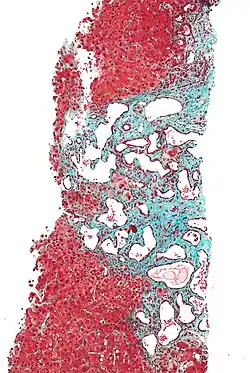

The cause of ARPKD is linked to mutations in the PKHD1 gene.[2] The PKHD1 gene encodes for the protein forfibrocystin, that is found in the epithelial cells of both the renal tubule and the bile ducts; deficiency leads to the characteristic polycystic dilation of both structures.[11]

It is capable of producing multiple alternatively spliced transcripts.[12] The largest known transcript encodes fibrocystin /polyductin (FPC), which is a large receptor-like integral membrane protein of 4074 amino acids.[12] The structure of the FPC consist of a single transmembrane, a large N-terminal extracellular region, and a short intracellular cytoplasmic domain.[12] The FPC protein is found on the primary cilia of epithelia cells of cortical and medullary collecting ducts and cholangiocytes of bile ducts, and show similarity to polycystins and several other ciliopathy proteins.[12] FPC is also found to be expressed on the basal body and plasma membrane.[12] It is presumed that the large extracellular domain of FPC binds to a ligand(s) that is yet unknown and that is also involved in cell-cell and cell-matrix interactions.[12]